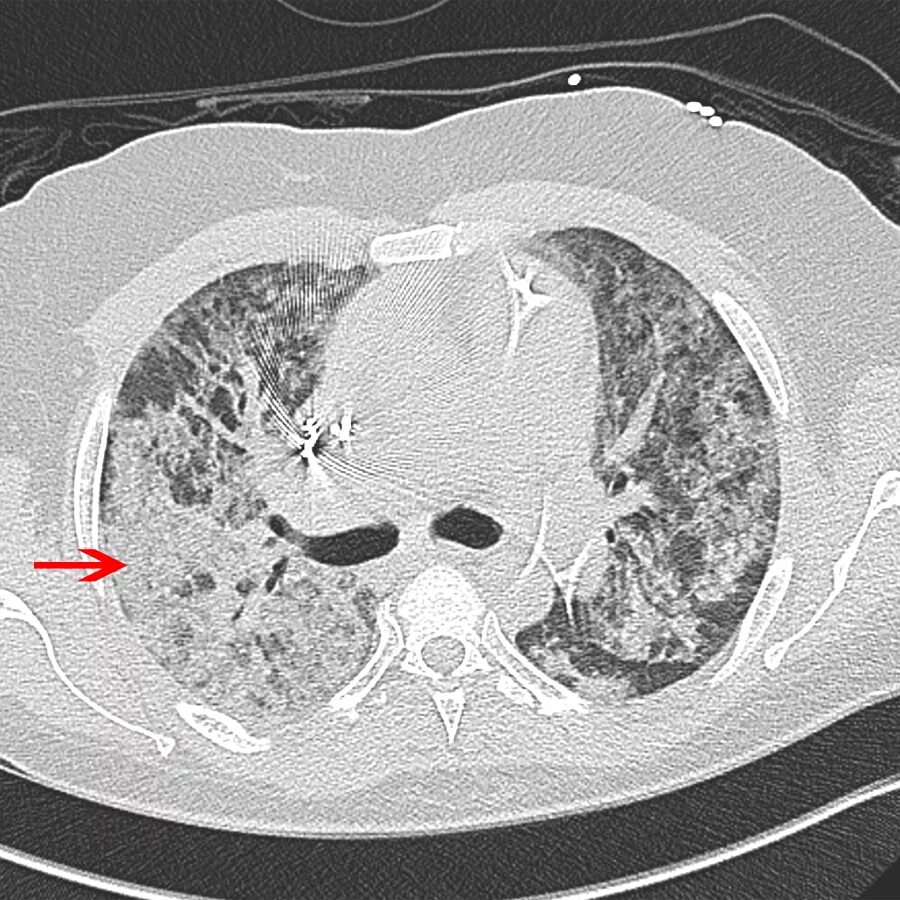

Ордс крипта